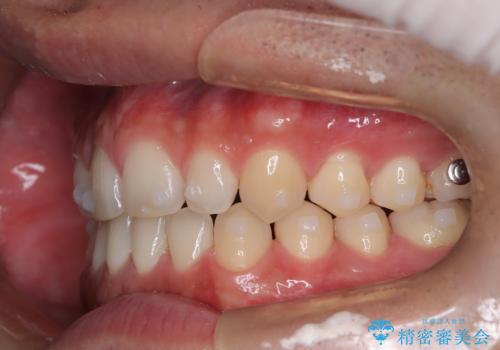

前歯の隙間が気になる マウスピース矯正

- 前歯がすきっ歯であることを気にされて来院された患者様です。上下顎のアーチを整える治療計画を立案し、マウスピースにて治療しました。とてもまじめに使用していただき、気になっていた隙間も順調に閉鎖しました。